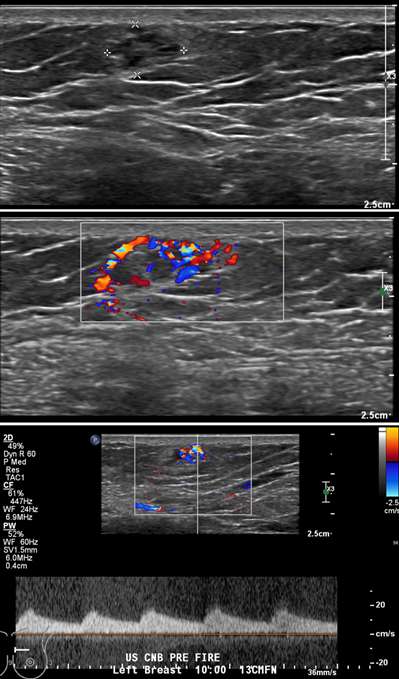

Figure 4A. Arteriovenous malformation. A 43 year-old woman presented for diagnostic left breast sonography after a focal asymmetry was seen in the upper inner quadrant of the left breast on routine screening mammography. Greyscale (top) and color Doppler (middle) images show a complex heterogenous vascular mass at 10 o’clock located 13 cm from the nipple, corresponding to the area of focal asymmetry. The patient later returned for a planned biopsy, however, pre-biopsy spectral Doppler (bottom) imaging demonstrated arterial waveforms within the mass consistent with a high-flow vascular lesion, thus, the procedure was aborted.